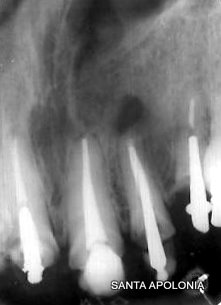

Paciente apresentou-se com lesão periapical veja RX inicial, foi indicada a cirurgia e no ato foi retirado material para exame histopatologico, para se descobrir a natureza da lesão.

Notar que a raiz do dente vizinho esta inclinada pela presença da lesão, suspeita de Cisto.O Cisto aumenta de tamanho sempre causando grande perda óssea, causando se não tratado deformidade óssea e dental podendo ser fatal.

Antes da Cirurgia

Após com redução da perda óssea